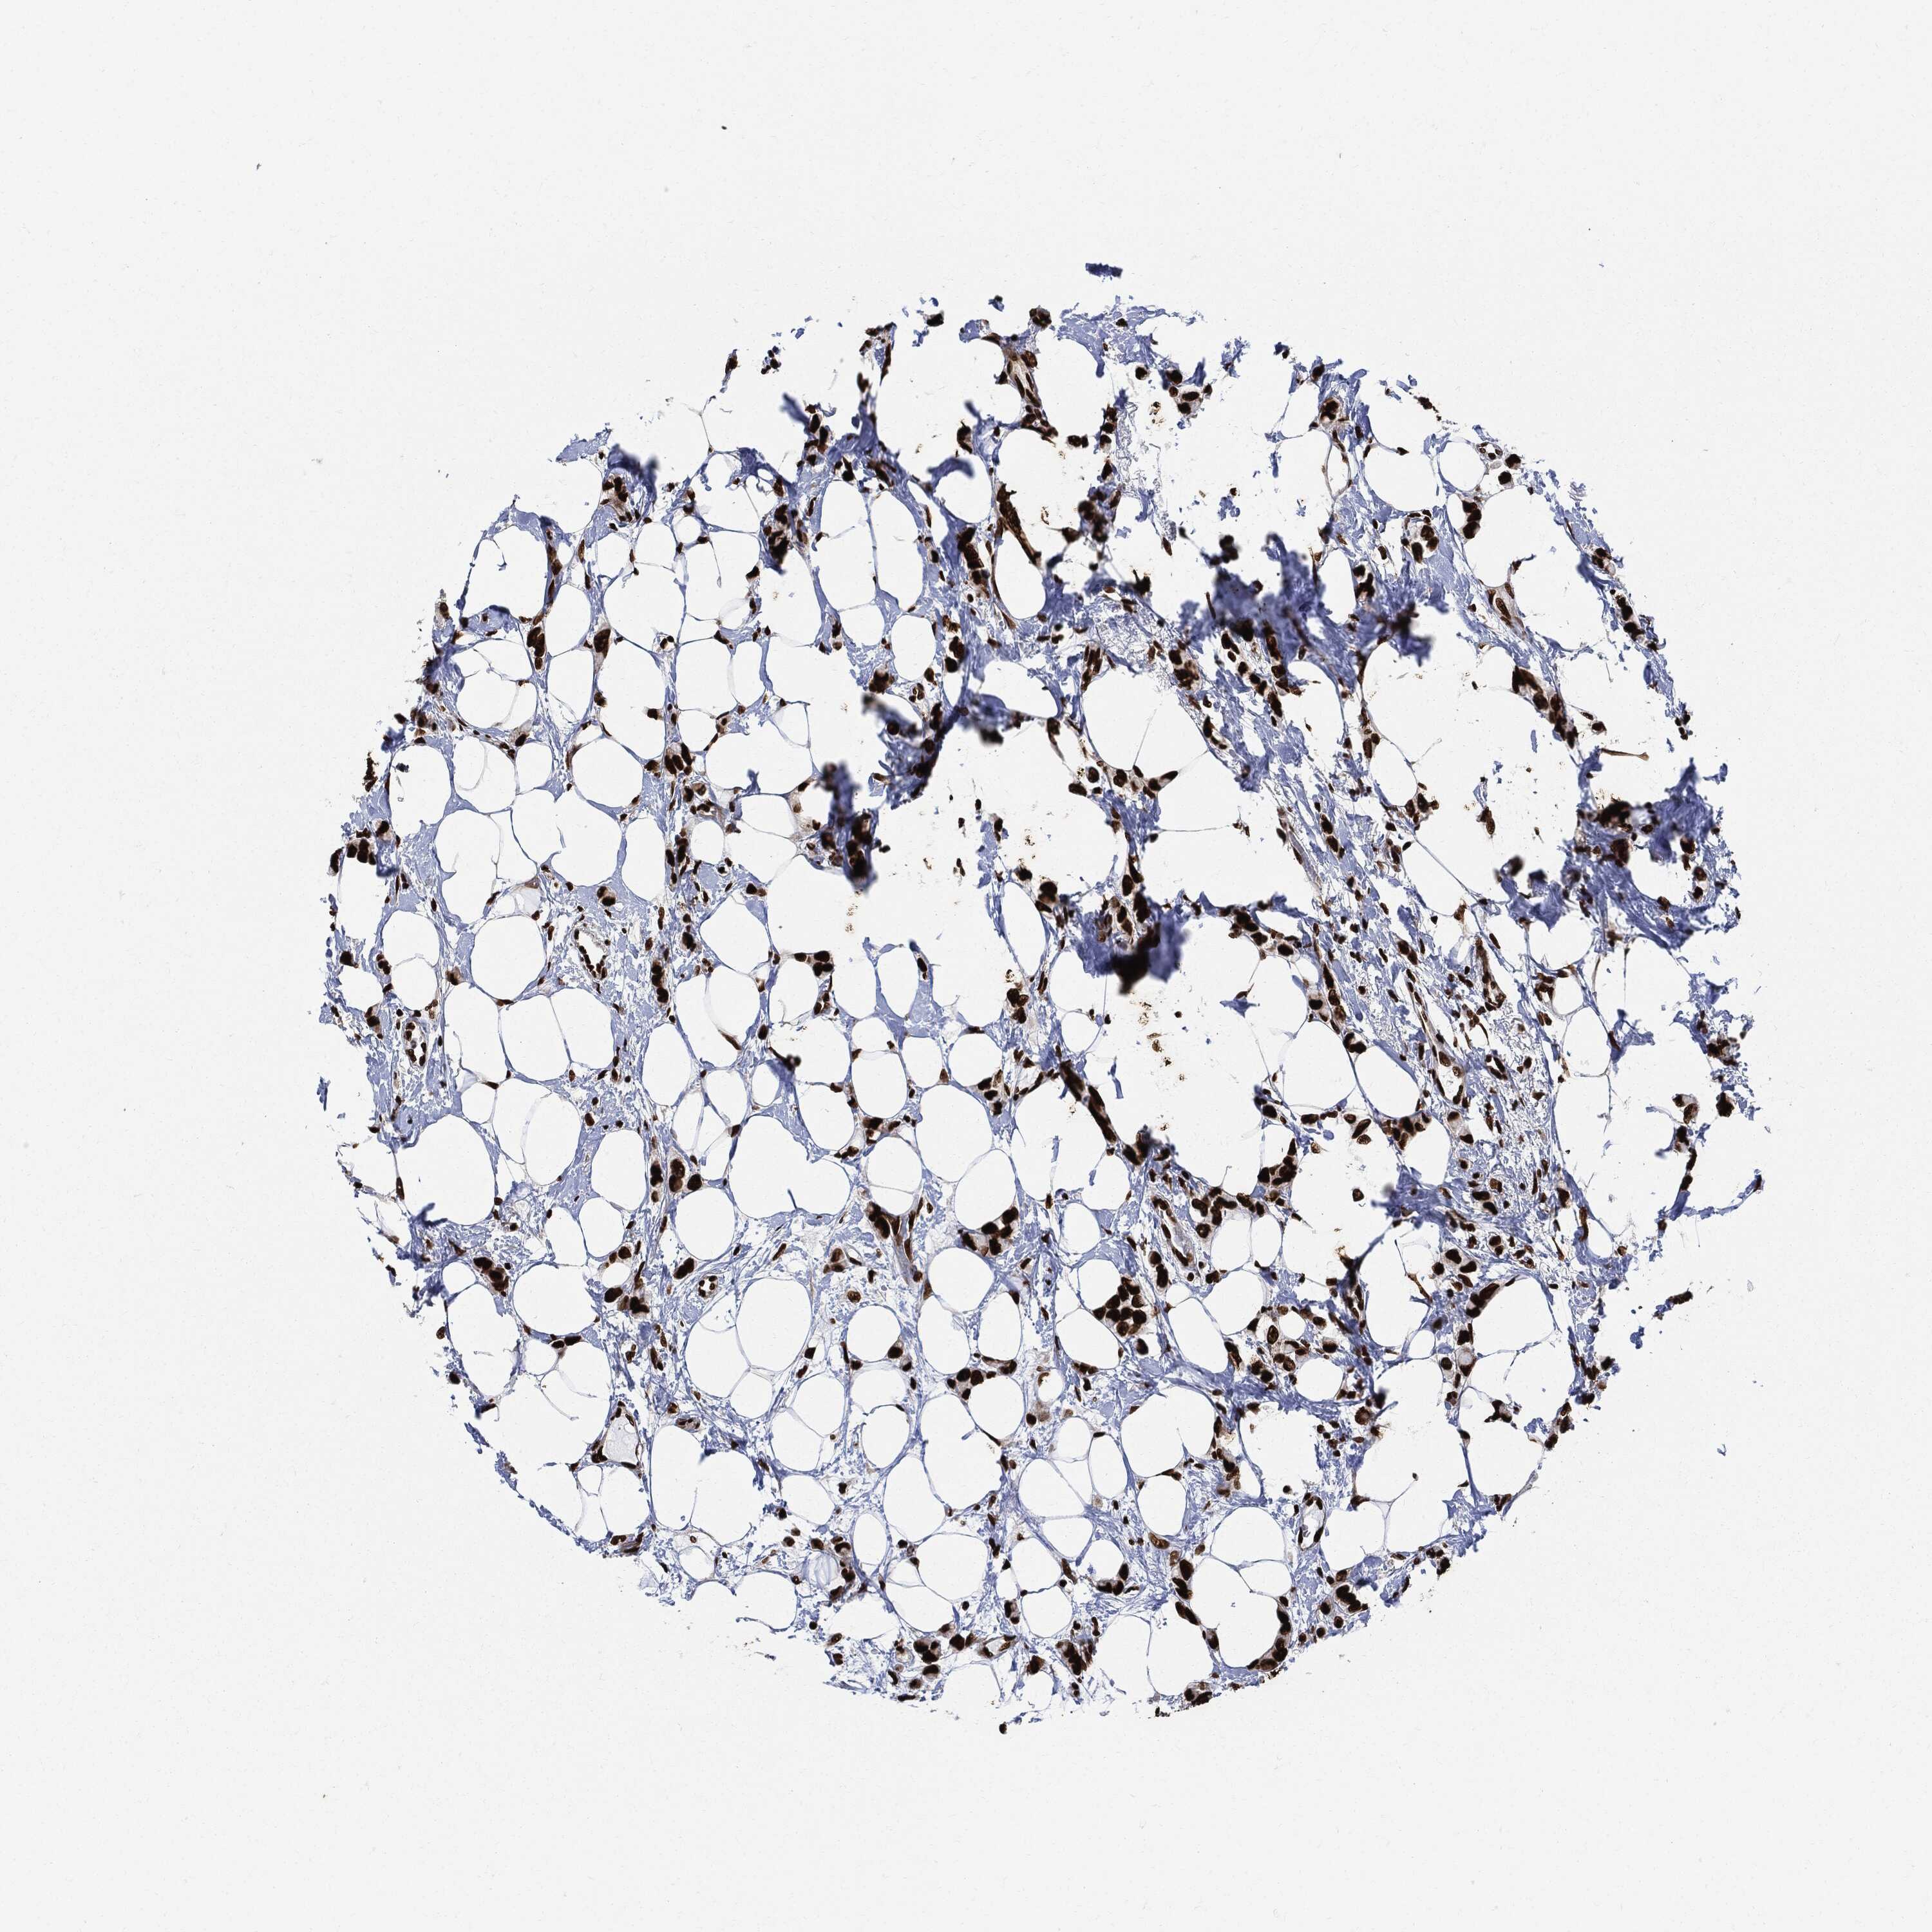

CANCER BREAST CANCER Show tissue menu

BRCA TCGA BRCA VALIDATION PROTEIN EXPRESSION

ANTIBODIES

AND

VALIDATION